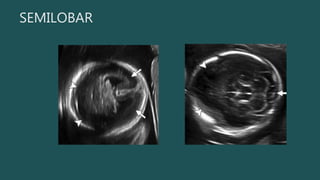

SEMILOBAR

Semilobar y Lobar El único hallazgo obvio por US a las 18-20 sdg sería la incapacidad de detectar el cavum septum pellucidum. • La malformación es semilobar si los lóbulos frontales están fusionados > 50%. • Hoz y fisura interhemisférica posterior y parte posterior del cuerpo calloso Hipotálamo y tálamo siempre fusionados SEMILOBAR

• #19 El diagnóstico prenatal de HPE alobar es bastante sencillo Semilobar y lobar pueden ser un desafío. In semilobar HPE, the interhemispheric fissure and falx cerebri may be present posteriorly and part of the corpus callosum may be seen in the region of the posteriorly sepa rated hemispheres , with the anterior extent corresponding to that of the interhemispheric fissure. somewhat arbitrary criterion used in postnatal imaging is that the malformation is semilobar if the frontal lobes are more than 50% fused

• #20 Semilobar HPE. (a) Axial oblique US image shows a continuous mantle of brain anteriorly (arrowheads) but posterior division into hemispheres (arrows). (b) More inferior axial US image in the same patient shows normal posterior fossa structures (arrow) below the tentorium but fused anterior supratentorial brain (arrowheads).

• #21 Semilobar HPE. (a) Coronal US image shows a monoventricle (*) and partial fusion of the thalami (T). (b) Coronal T2-weighted half-Fourier RARE MR image shows the continuous anterior brain parenchyma (arrow), monoventricle (*), and partially fused thalami (T). (c) Coronal T2-weighted half-Fourier RARE MR image more posteriorly shows two occipital lobes separated by the falx (arrow).